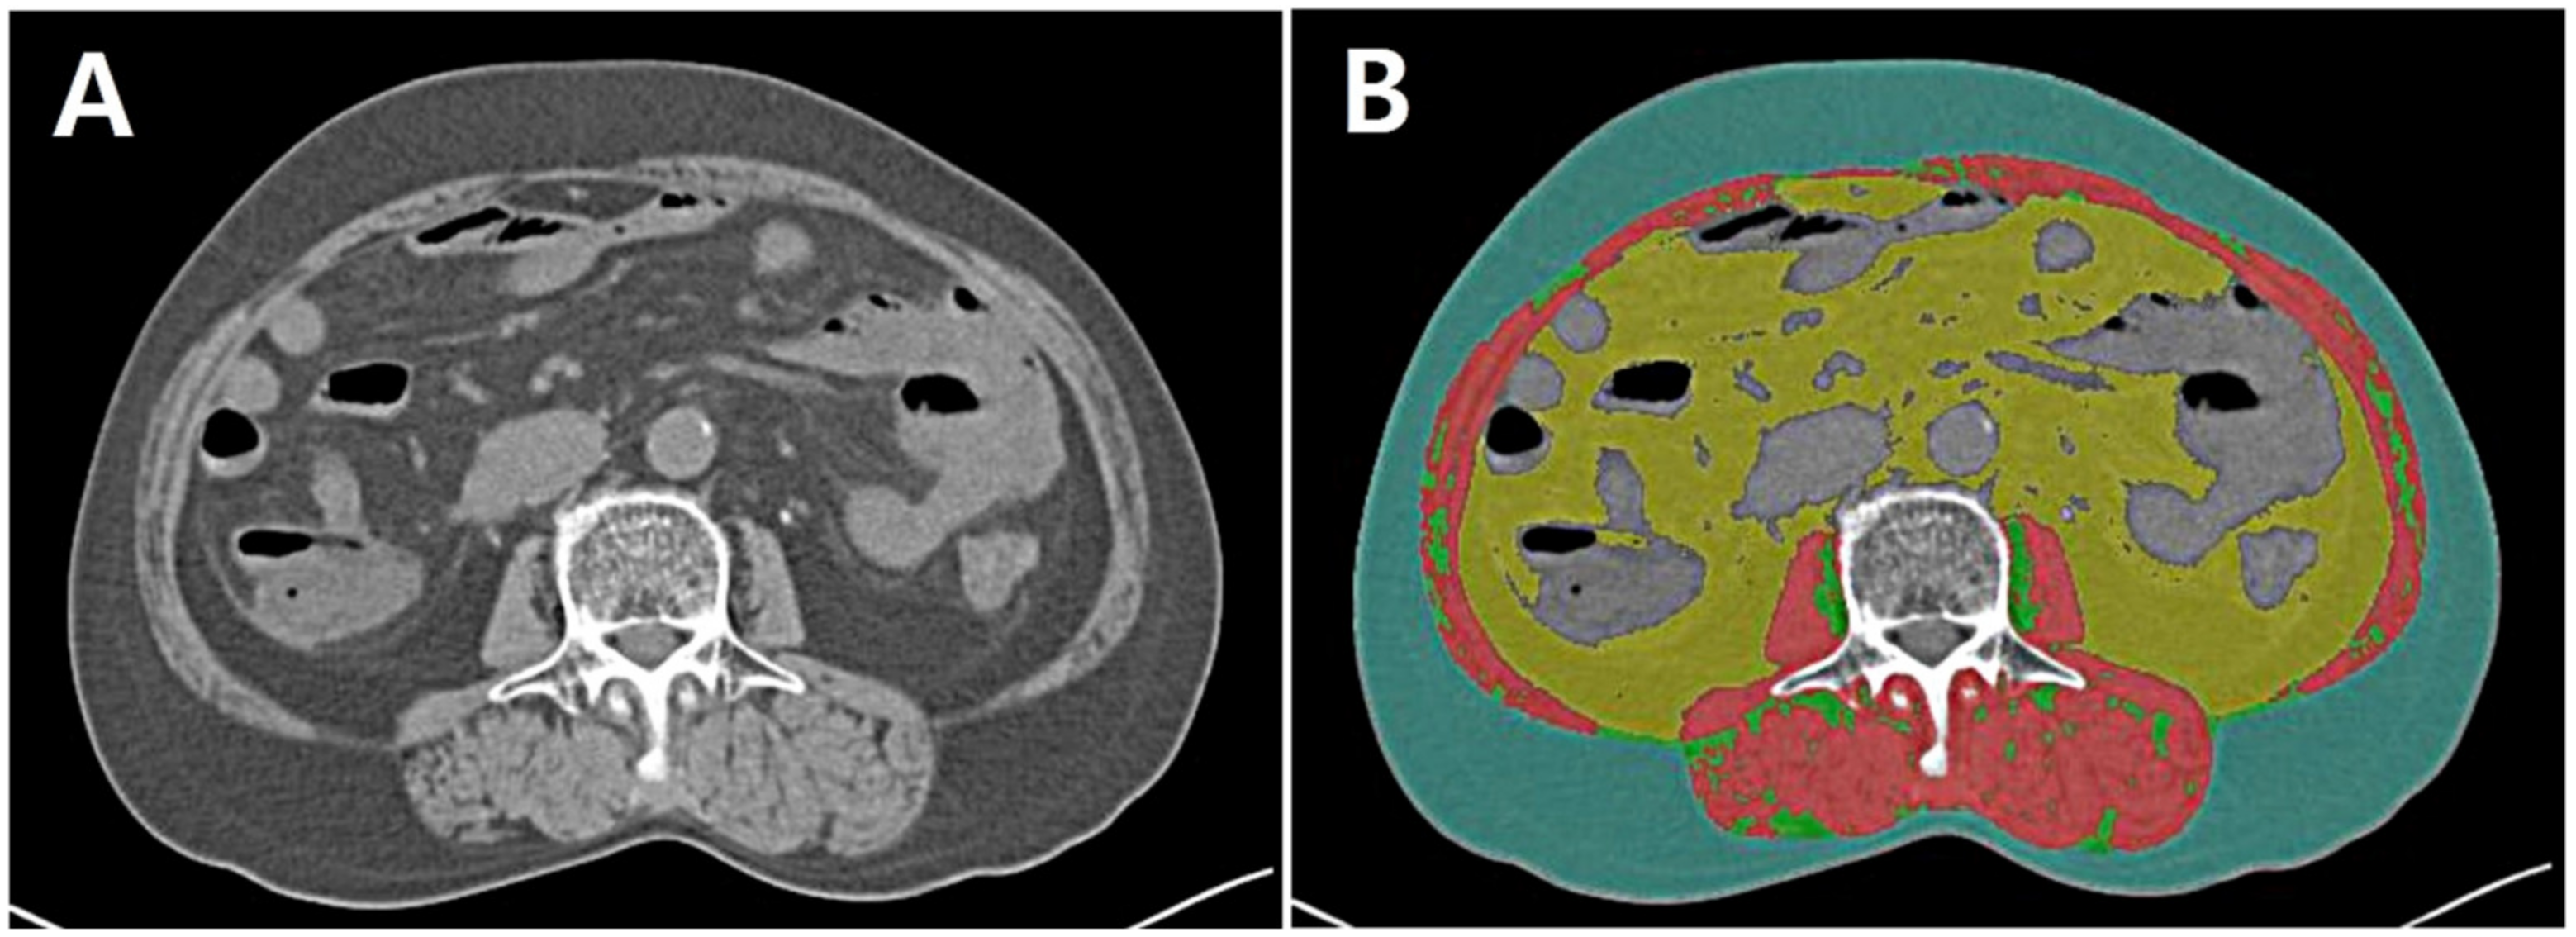

2.3. Assessment of Body Composition Data

- Paris, M.T.; Tandon, P.; Heyland, D.K.; Furberg, H.; Premji, T.; Low, G.; Mourtzakis, M. Automated body composition analysis of clinically acquired computed tomography scans using neural networks. Clin. Nutr. 2020, 39, 3049–3055. [Google Scholar] [CrossRef]

| Body composition analyses based on CT | |

| SMI, cm2/m2 | 49.4 [43.0–58.1] |

| VATI, cm2/m2 | 42.7 [23.5–62.7] |

| SATI., cm2/m2 | 36.7 [24.6–51.7] |

| HU | 53.7 [48.3–56.6] |

| VSR | 1.1 [0.8–1.5] |